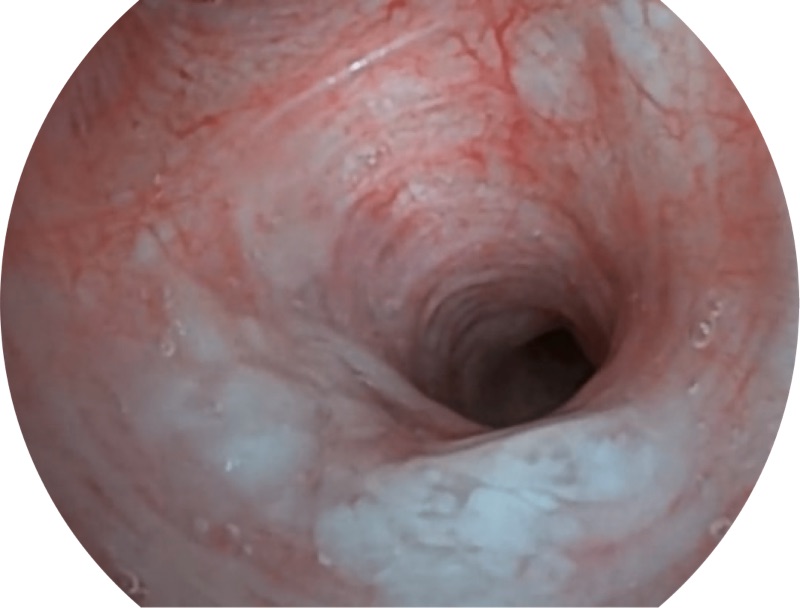

白光